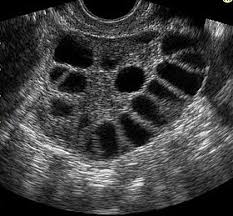

"Polycystic ovary syndrome (PCOS) is a common hormonal disorder among women of reproductive age. The name of the condition comes from the appearance of the ovaries in most, but not all, women with the disorder — enlarged and containing numerous small cysts located along the outer edge of each ovary (polycystic appearance)."

So in a women's terms: PCOS is a disease in women when cyst on the ovaries can prevent the women from ovulating. The cyst can be caused, as in my case, by insulin resistances or hormonal imbalance. The cyst are basically follicles that can't mature completely because of a lack of hormone so instead they become the spons of the devil. This is usually where Clomid comes in to aid in your hormonal production to help you mature those oh-so-precious follicles that could potentially change your life...As pictured above, cyst pretty much look exactly like that! Fun,I know! You may be wondering what these cyst do after awhile of taking a vaca on your tab....well they can eventually decrease in size or burst and cause pain you'd never wish on your worst enemy.